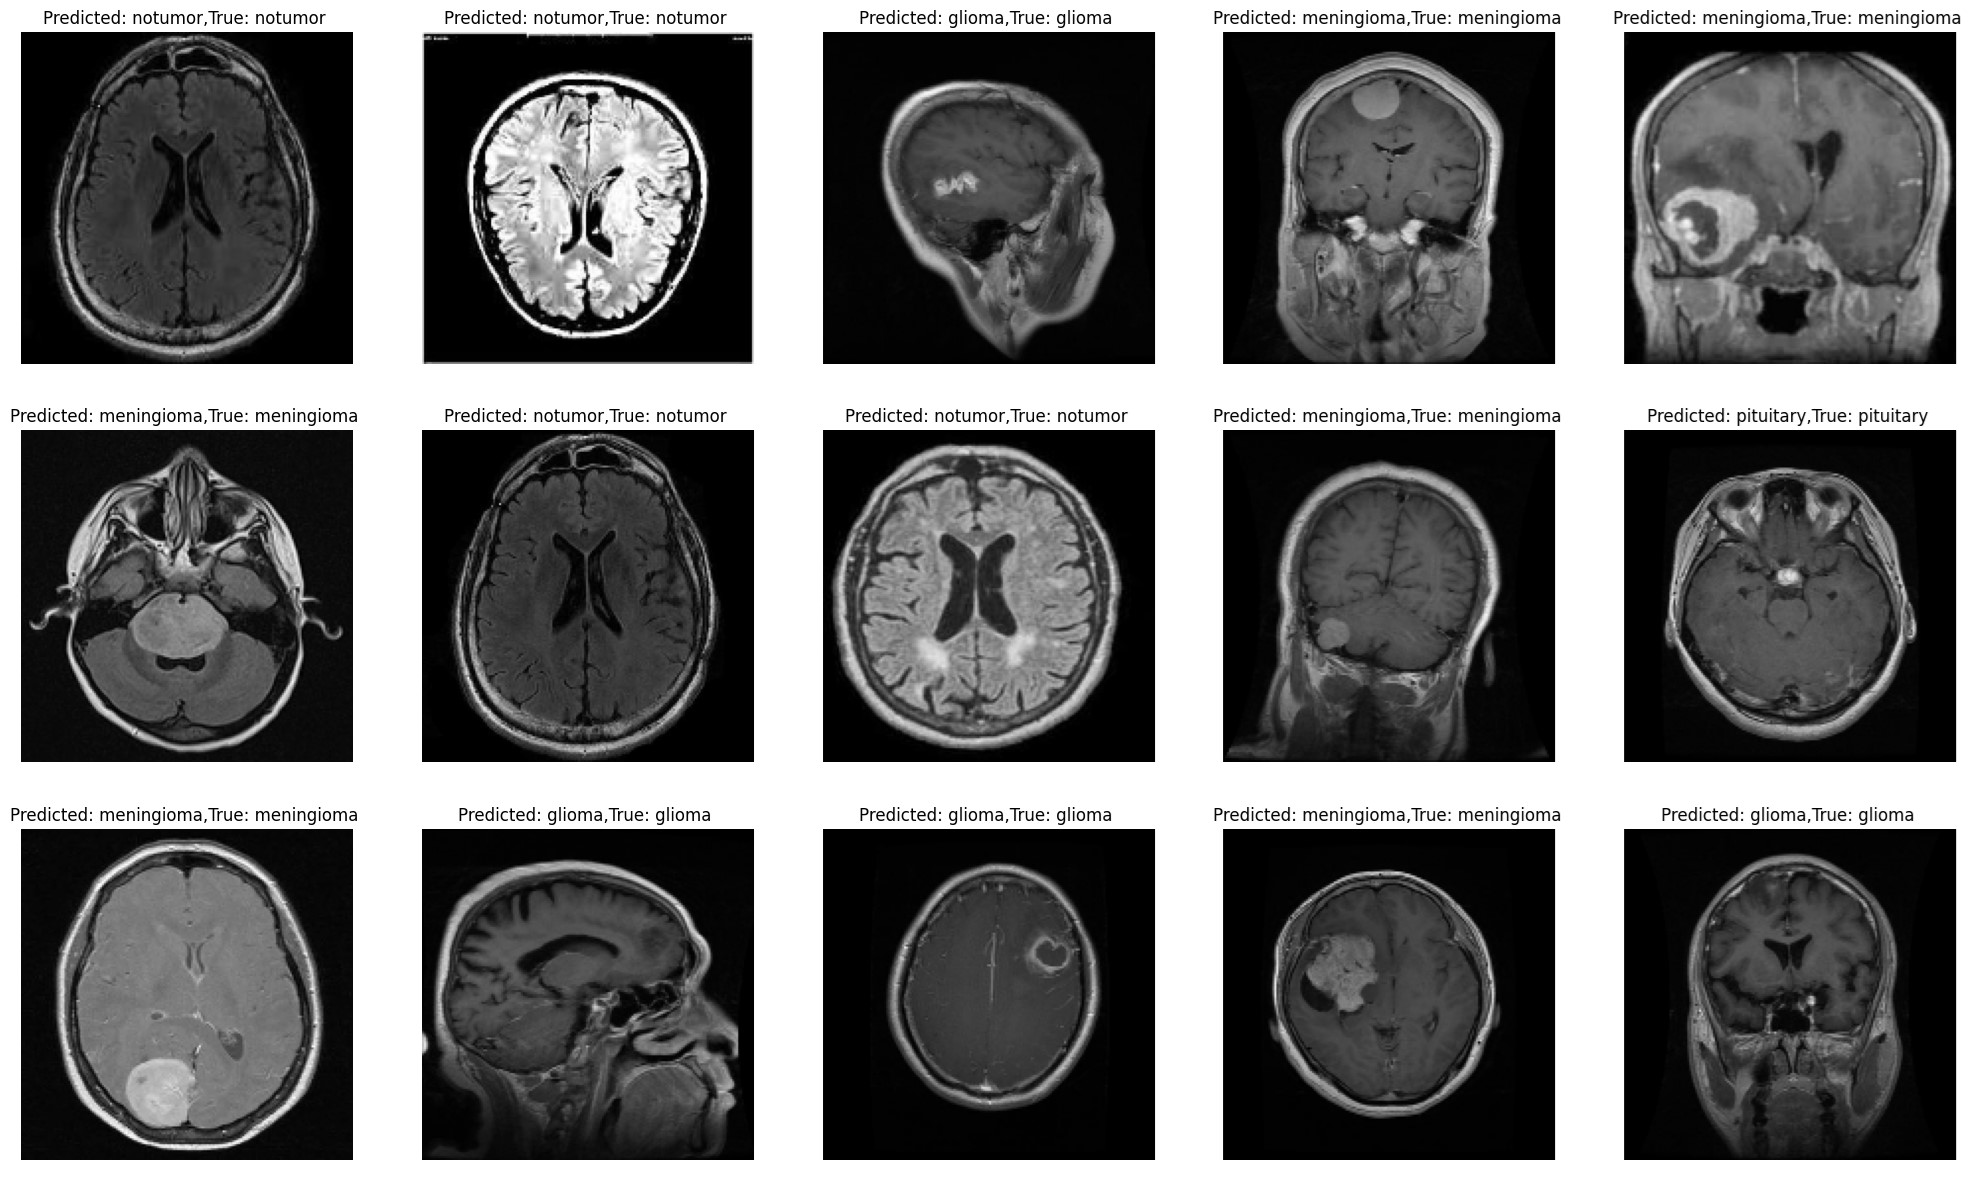

Brain Tumor MRI

Implemented classification of brain tumors using ANN, DNN, and CNN with Python, achieving an F1 Score of 92%.

Deep Learning Keras Tensorflow Python